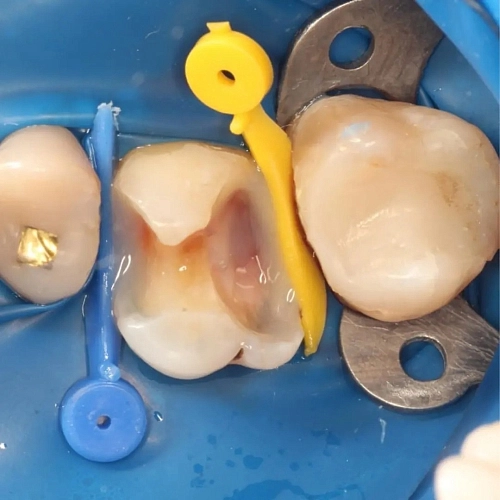

На фотографии представлена работа врача стоматолога Морозовой Александры Сергеевны, где зуб успешно подготовлен к дальнейшему протезированию.